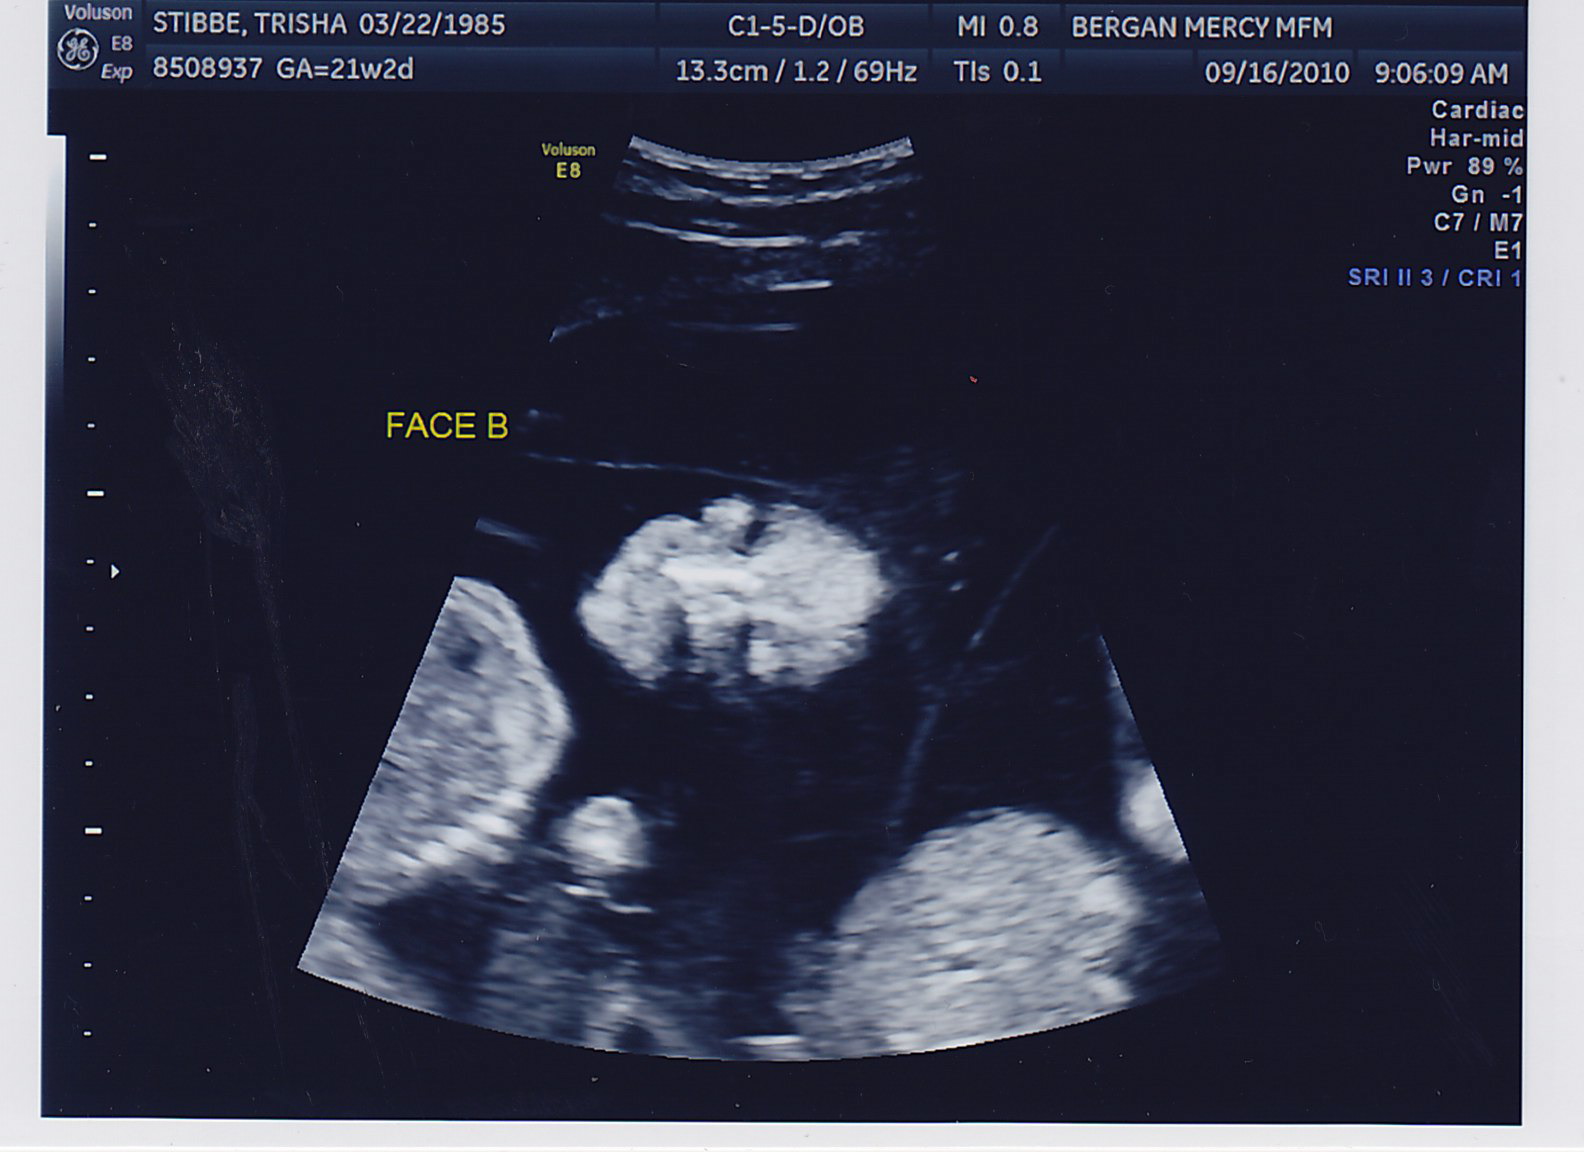

Another successful appointment! Both boys gained weight, we could see the bladder on Baby B (something the doctor needs to keep a close eye on) and the fluid levels in both looked great. No amnio therapy for Mommy today! Here are some more pictures of the little peanuts, who were called “photogenic” by the sonographer today <– very proud Mom-moment 🙂